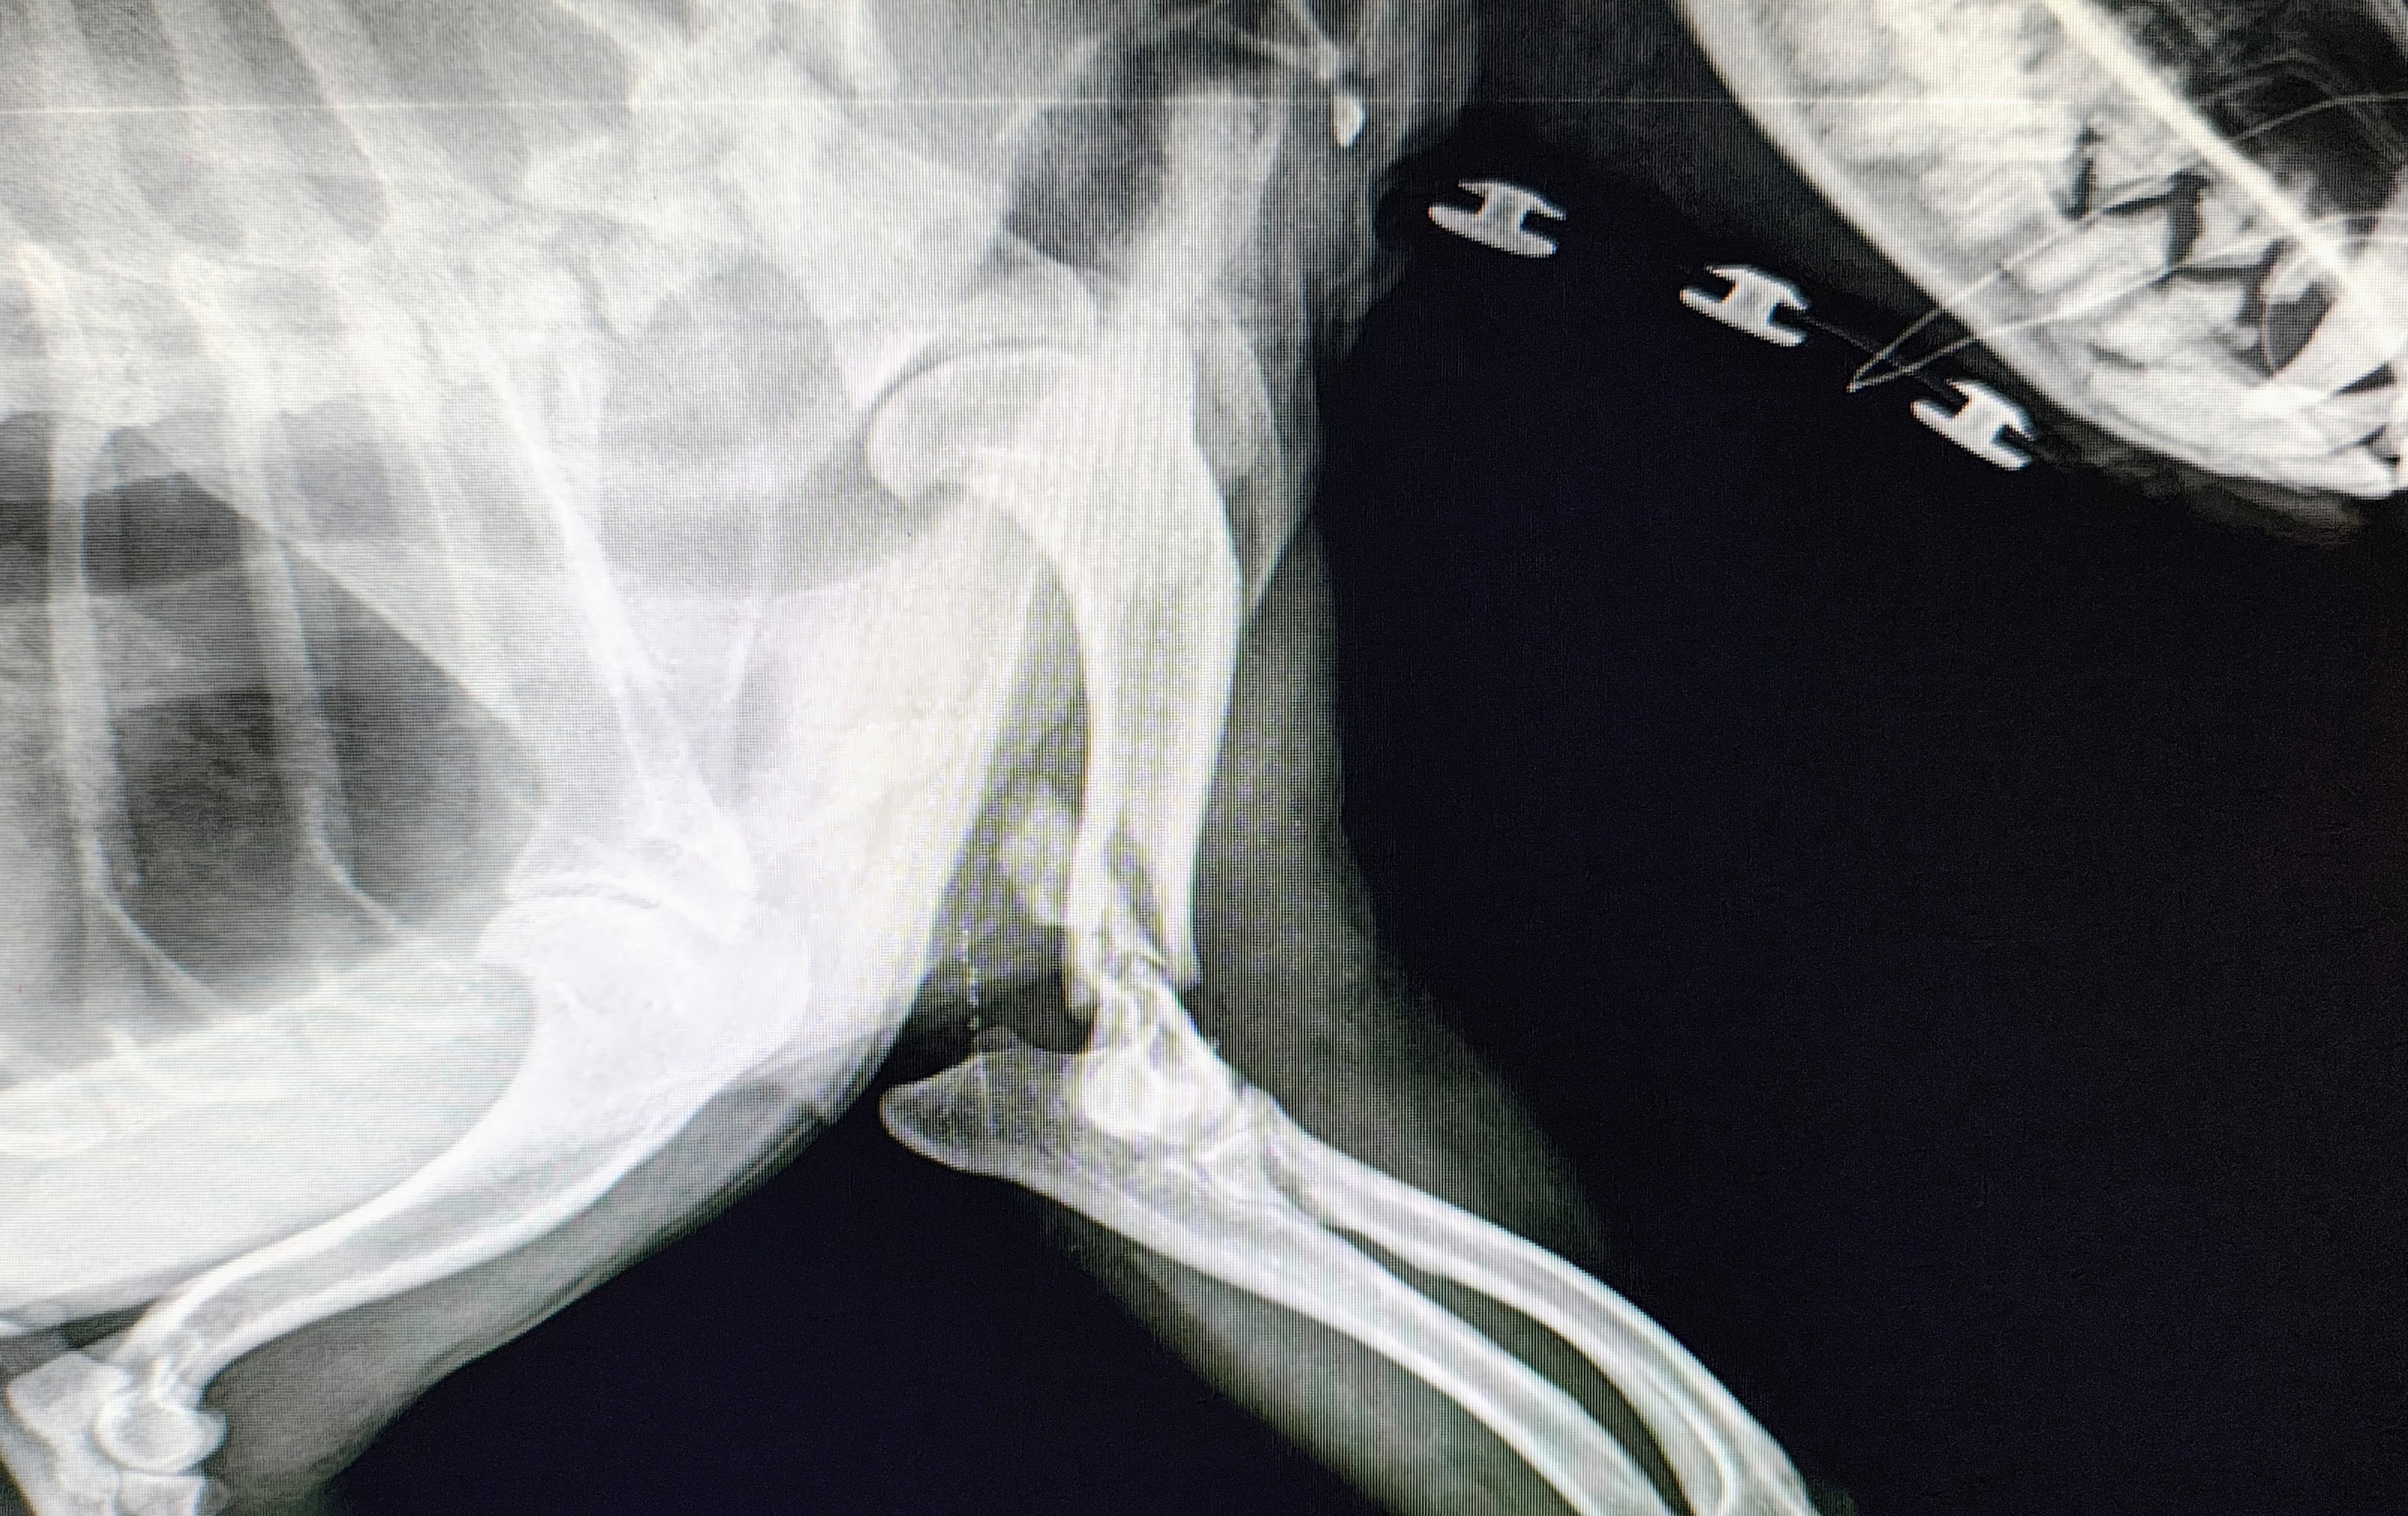

Hoy fui a ver a Friky a la Veterinaria Patas Descalzas. Despertó de la anestesia y está muy bien. En las nuevas radiografías ya se aprecio mejor y a detalle sus fracturas, que fueron en 3 partes. Entonces ya autoricé para que se le realice la cirugía indicada, que se realizará el Jueves 25 y se quedará todavía hasta el Lunes 29 para estar en observación y recuperación. El total de todo el proceso se me costeo al final a 7000 MXN, hoy pague la mitad y con sus donaciones terminaré de pagar lo que falta y para comprar medicamentos que se me indiquen para su tratamiento que falte. Nuevamente les agradezco a todos los que me apoyaron, yo sé quiénes son, así que estoy eternamente agradecido, no solamente yo, también Friky. Aún así los mantendré al tanto de lo que suceda en próximos días. Saludos!